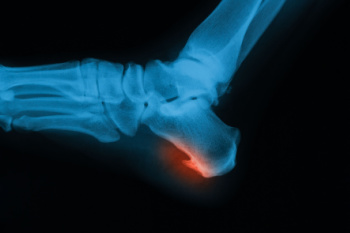

A heel spur is a calcium deposit that forms under the heel bone, often linked to ongoing strain on the foot. Although the spur itself may not always cause pain, the surrounding tissue can become irritated. Recovery focuses on reducing pressure and inflammation. Wearing supportive shoes with good arch structure, cushioned insoles, and soft heel pads can make a big difference. Stretching the calf and foot regularly helps ease tension along the bottom of the foot. Avoiding high-impact activities allows the area to calm down. In some cases, custom orthotics or targeted exercises may be helpful. While quick relief is possible with the right care, complete healing may still take time. If your heel pain does not improve or becomes more intense, it is suggested that you see a podiatrist for a proper diagnosis and a personalized treatment plan.

Heel spurs are formed by calcium deposits on the back of the foot where the heel is. This can also be caused by small fragments of bone breaking off one section of the foot, attaching onto the back of the foot. Heel spurs can also be bone growth on the back of the foot and may grow in the direction of the arch of the foot.

Older individuals usually suffer from heel spurs and pain sometimes intensifies with age. One of the main condition's spurs are related to is plantar fasciitis.

The pain associated with spurs is often because of weight placed on the feet. When someone is walking, their entire weight is concentrated on the feet. Bone spurs then have the tendency to affect other bones and tissues around the foot. As the pain continues, the feet will become tender and sensitive over time.